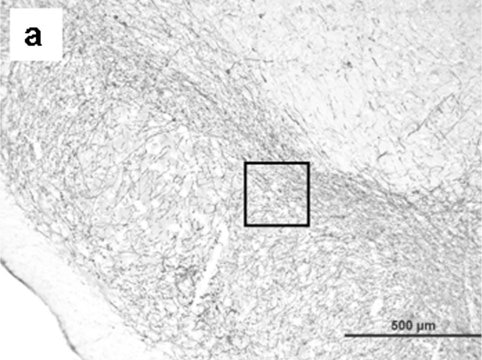

Immunohistochemistry:

A previous lot of this antibody was uesd at 1:100-1:1,000 dilution, 4°C, for 1-3 days. Stains both fresh frozen and paraffin embedded tissue samples by indirect immunofluorescence and immunoperoxidase.

POSITIVE CONTROL: Brain (corpus striatum, sympathetic nerve terminals) and adrenal glands.